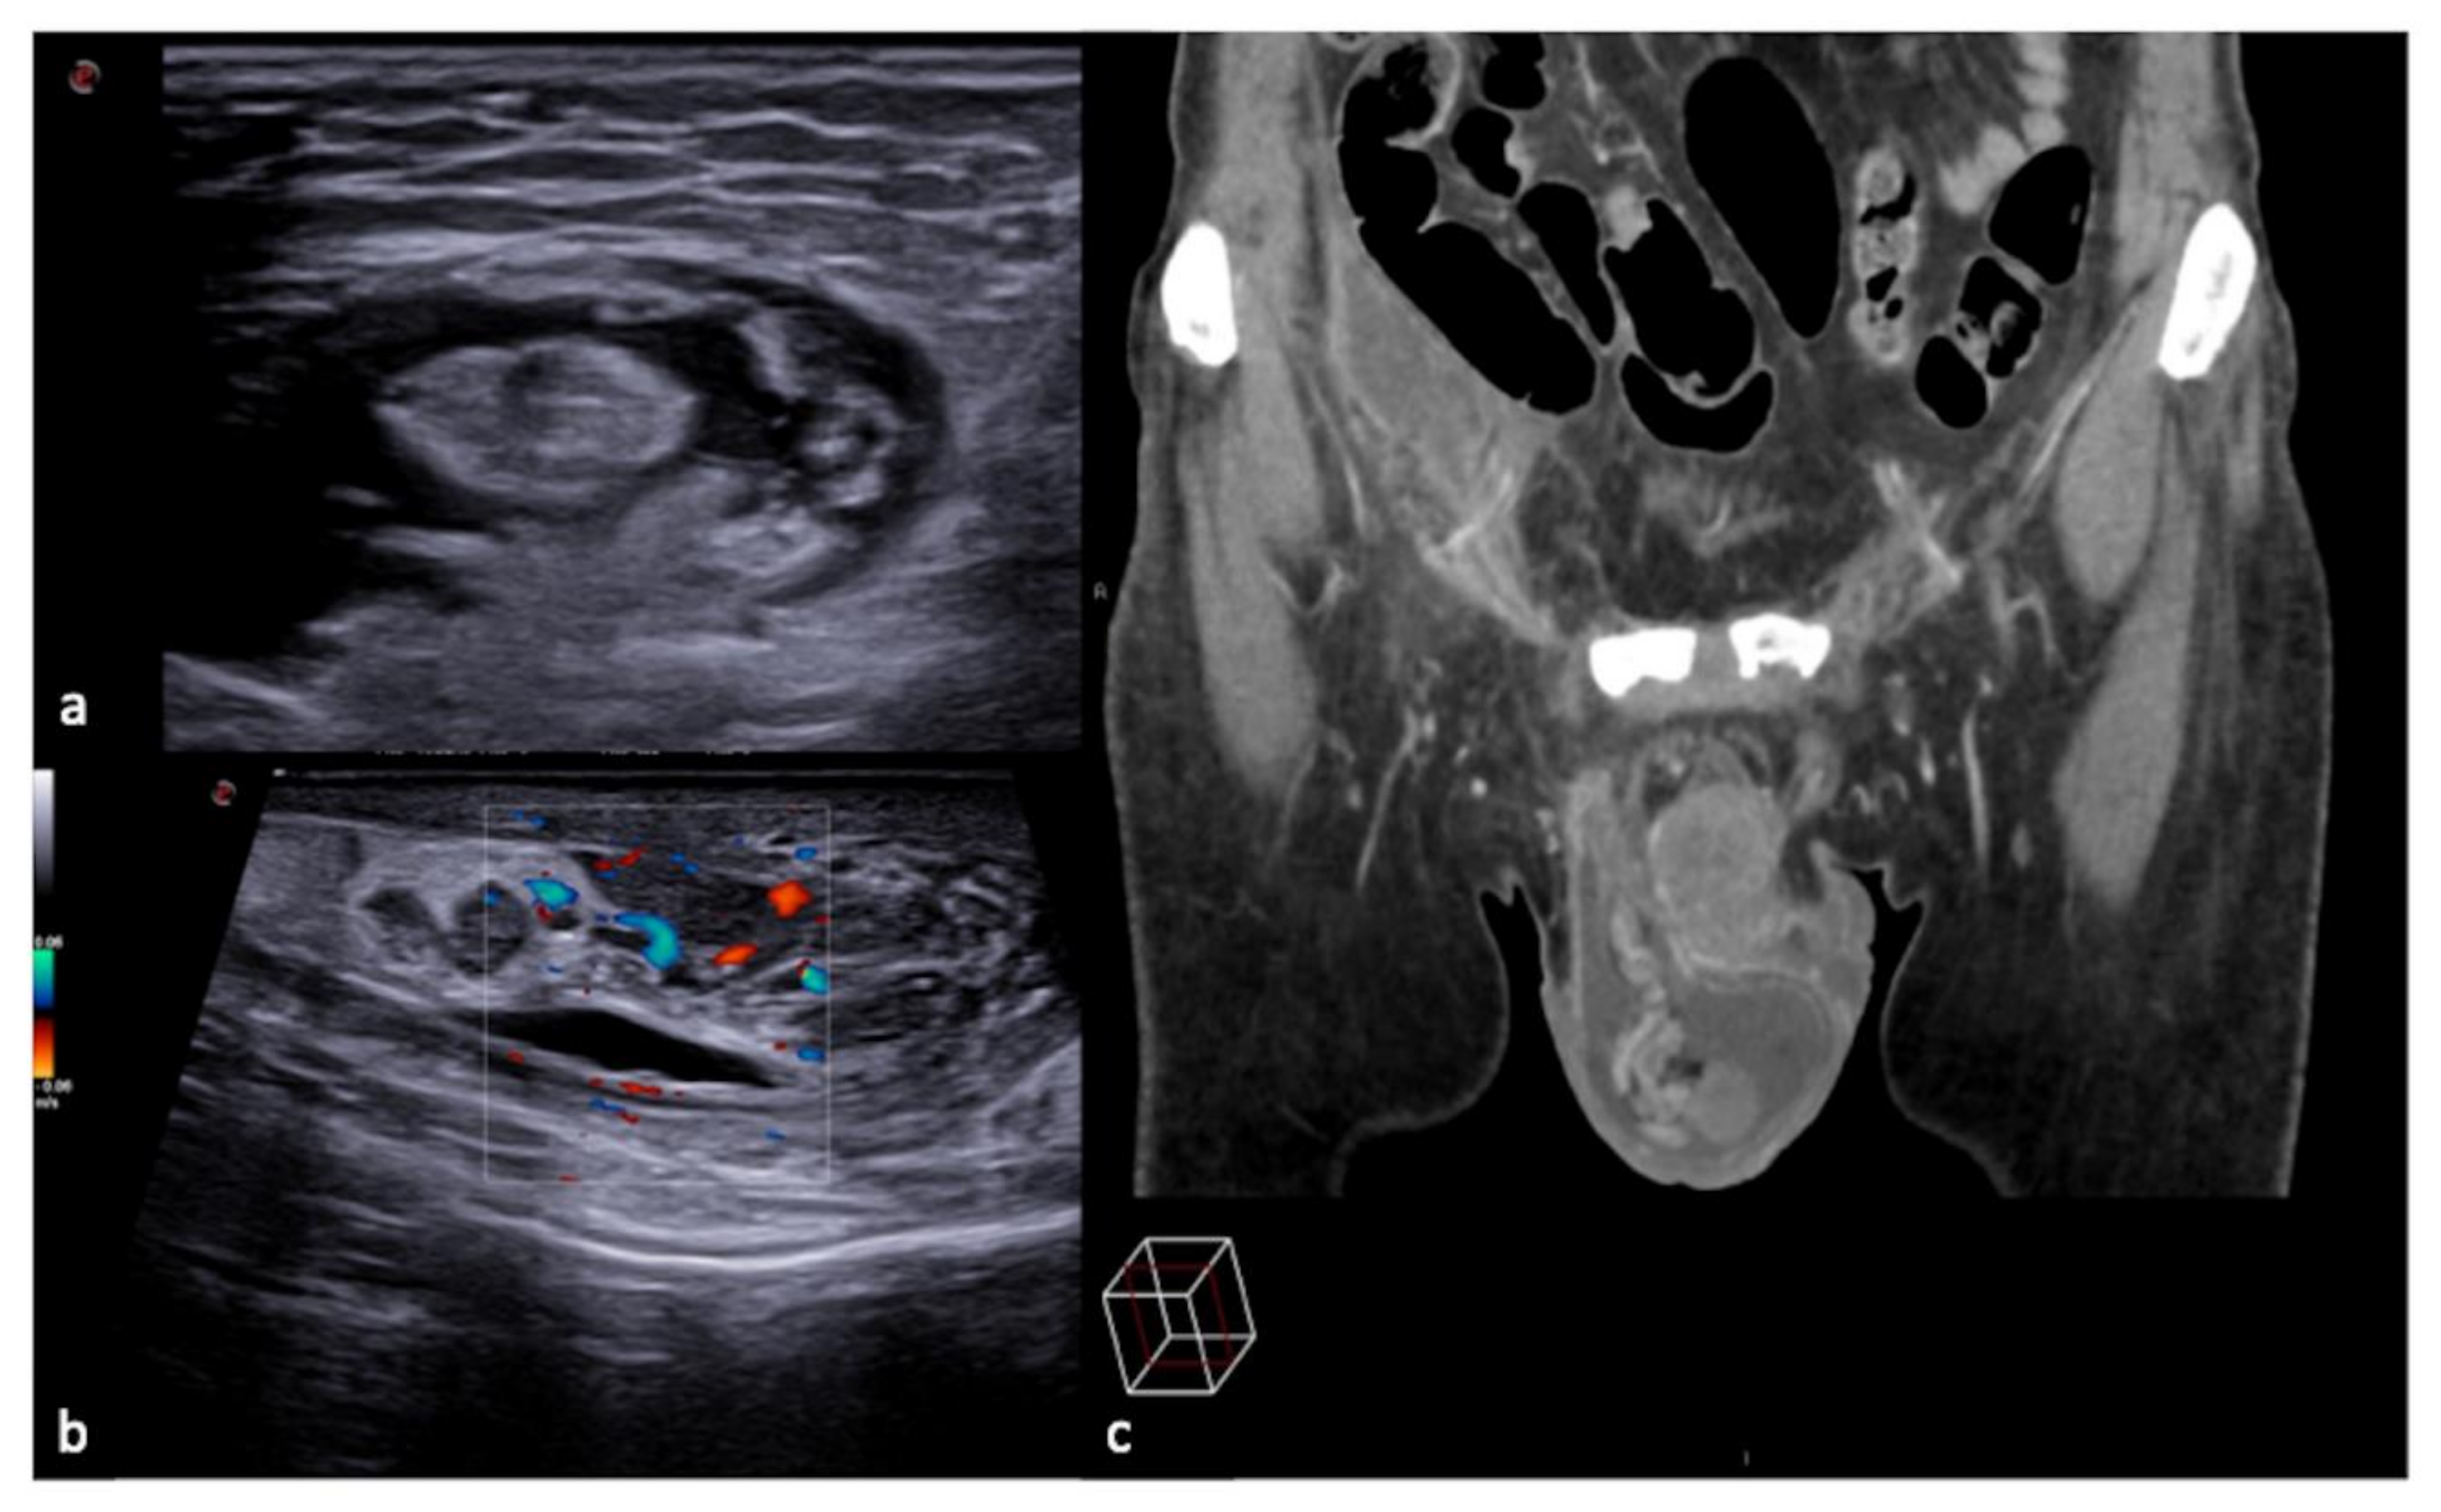

3.1.2. The Mirror-Imaging Effect